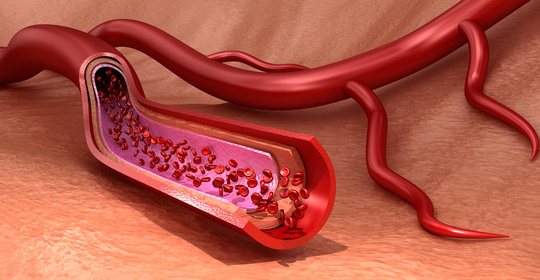

早產兒貧血:發病機制、診斷及補充治療